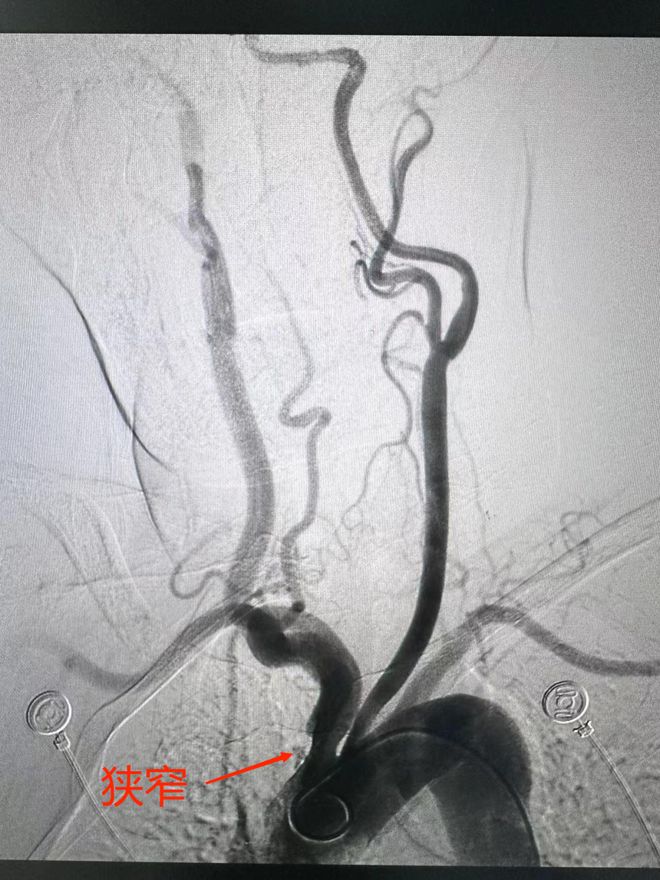

磁共振血管造影是一种利用核磁的流空效应来显示血管的新技术,其操作过程主要包括以下步骤采集图像资料首先,通过磁共振设备采集一系列连续薄层的断面图像资料这些图像资料是后续进行血管重建的基础图像后处理采集完图像资料后,需要...